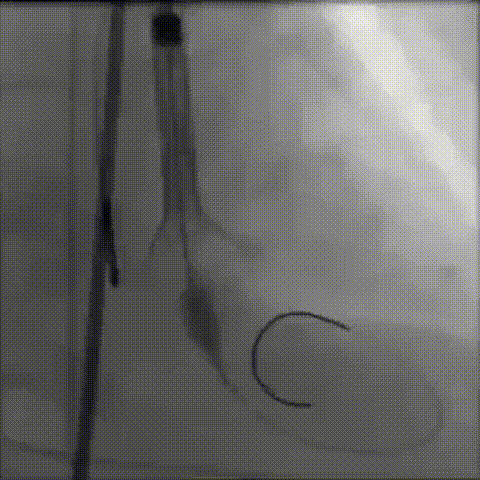

主动脉根部造影

输送器顺利过弓、跨瓣

瓣膜标准位定位

瓣膜释放到工作位

工作位造影

位置理想,瓣膜完全释放

释放后造影

外周造影无狭窄闭塞